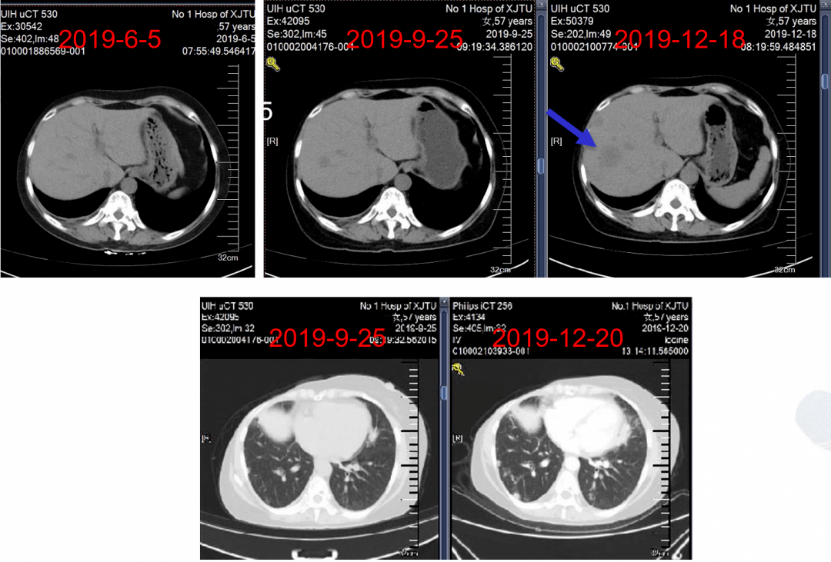

病情演变:2019年12月18日,随访影像学显示肝脏转移病灶可能(图8)。

图8:一线治疗期间随访肝脏及肺部病情演变